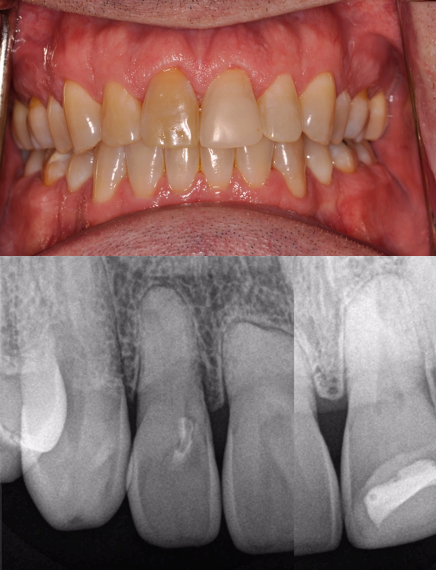

Figure 26 shows a full-arch classic "All-on-X" case at presentation. The patient was a 66-year-old male with a mutilated dentition. The patient had lost vertical dimension and desired a fixed restoration. Options were discussed with the patient, including dentures, which the patient refused long term. The patient instead agreed to a plan to undergo extractions of his remaining dentition and have an immediate maxillary denture with five mandibular implants and an immediate mandibular hybrid denture. The practitioner worked with a laboratory that could provide a monolithic PMMA digitally milled denture. Two months following implant treatment of the mandibular arch, the patient had six maxillary implants placed with immediate denture conversion.

Intra- and extraoral photographs, intraoral scans, and analog impressions were taken and a CBCT was acquired. A digital smile design was accomplished and records sent to the laboratory (Figure 27). The digital records and analog models were scanned and imported into the digital denture scanning software that was used to plan the denture. The denture plan was then imported into the implant planning software (Nobel DTX Studio, Nobel Biocare; alternatively: X-Guide, X-Nav Technologies; Implant Studio, 3Shape) to create the plan for the implants (Figure 28). Next, the plan was imported into the navigation software system of the navigation unit, and the practitioner was able to begin planning bone reduction and screw positions.

At the time of surgery, the maxillary dentition was removed, bone grafts were placed, and an immediate denture was relined in the predetermined occlusion using an occlusal stent. Next, a crestal incision was made in the mandible. The fixation screws were then placed below the level of the planned bone reduction. The tracker arm was placed on the platform of the screws and the nuts tightened to rigidly fixate the patient tracking arm. The tracker array was then tightened into place. The arm of the tracking array additionally assists as it retracts the lip. Next, the patient was registered anatomically by touching the teeth in the predetermined locations. A system check was performed to verify the accuracy of the tracking system. No refinement was necessary. Bone reduction was then accomplished using a straight handpiece under navigation, and the implants were placed. The prosthodontist then used temporary cylinders and picked up the positions of the implants using the milled mandibular transition appliance. The occlusal locks at the distal of the prosthesis assured that the correct vertical dimension was obtained (Fig- ure 29). The incision was closed, and the denture was finished in the laboratory and delivered the next morning.

The hybrid denture was delivered the next day. After 2 months, the patient was seen again, and the practitioner performed osteo- tomies and placed six maxillary implants. Figure 30 is a retracted view of the patient's dentition 1 week postoperatively. For both the mandible and maxilla together, the mean angular deviation was 2.08 (SD, 0.85), the mean platform deviation was 0.97 mm (SD, 0.43), and the mean apical deviation was 1.25 mm (SD, 0.44), which is within the expected range. With the help of dynamic navigation, the procedure was extremely successful. Figure 31 shows the patient's digitally milled PMMA prosthesis and soft tissue at 1 year postoperatively.

Fig 26. Mutilated dentition in an edentulous patient.

Figure 26

Fig 27. Digital smile design, intraoral view.

Figure 27

Fig 30. Retracted view of the patient’s dentition at 1 week postoperatively.

Figure 30

Fig 31. Final PMMA digitally milled prosthesis at 1 year postoperatively.

Figure 31